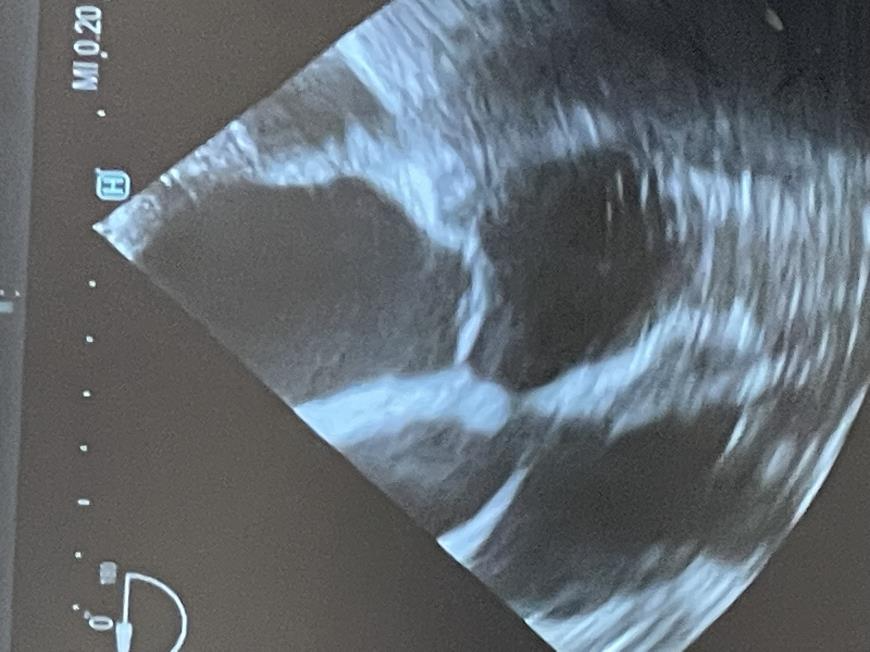

Fotoğrafta midventricular HCM bulunan bir hastamdaki Ekokardiyografi görüntüsünde sol kalbin orta ve alt kesimlerinde (midventricular HCM), septal ve posterolateral duvarların kasılma anında birbirleri ile çarpışmakta olduğu görülüyor. Bu durum kalp içinde akıma engel olarak yüksek tansiyon yaratmakta, kalp duvar gerginliğini ileri derecede artırmaktadır. Giderek artan kalp içi basıncı ve duvar gerginliği kalp kasını daha da kalınlaştırmakta ve kalp yetersizliğinin temel mekanizmasını teşkil etmektedir.

The echocardiographic image shows the septal and posterolateral walls of the left heart (midventricular HCM) colliding during contraction. This situation creates high blood pressure inside the heart because the flow inside the heart is blocked. This in turn causes the heart wall to become tense,  contributing to heart failure in people with HCM.